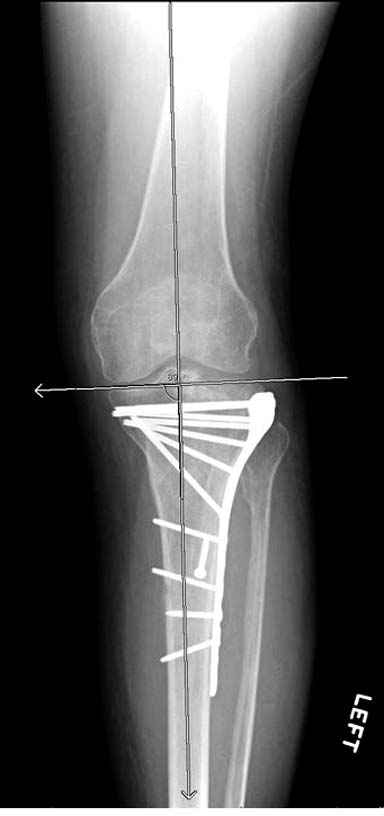

На вашем место я бы подождал с фиксацией до готовности кожных покровов, и за это время можно было подобрать соответствующий фиксатор, т.е более длинная пластина снаружи и медиальная пластина на апексе перелома как подпорка. Здесь приемлем как раз минимальный доступ.

Имеющаяся импрессия не потребовала пластики - достаточным оказалось поднять отломок

Если там действительная импрессия, пустое место без структуральных заполнителей, кость или синтетические материалы, не восстановится, а образуется коллапс, и ось конечности поведет после нагрузки. Кроме того там возможно "болт стяжка"?, в медиальной стороне выступает за кортекс, можно было укоротить! Потом создается впечатление, что не соответствуют мыщелки большеберцовой и бедренной костей? Покажите снимок.

Здесь пару случаев для сравнения,...в первых 1-4 слайдах метод фиксации одним фиксатором, как видно после 8 месяцев сохранилась ось. С 5 по 9 вариант двумя пластинами...